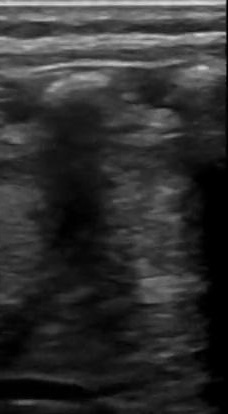

Lactante de 2 años sin antecedentes médicos o quirúrgicos conocidos, con esquema de vacunación completa, refieren los padres 3 días de presentar fiebre de hasta 39 ºC, continua y tos. Al Examen físico con buen estado general, llanto fácil pero consolable, activo y reactivo. Tórax: no tirajes costales, a la auscultación pulmonar con subcrepitante en base pulmonar izquierda e hipoventalación en zona lateroexterna basal izquierda. Se solicita radiografía de tórax en la que hay dudas sobre posible infiltrado basal por lo que se realiza ecografía pulmonar en la que se evidencian líneas B y pequeño derrame pleural.

La ecografía pulmonar es una herramienta valiosa para el diagnóstico de neumonía en niños, mostrando características específicas como consolidación, broncograma aéreo, líneas B y posibles derrames pleurales. Estos hallazgos nos ayudan a diferenciar entre diferentes tipos de neumonía, a evaluar la gravedad del estado del paciente y a resolver dudas radiológicas, sin embargo, lo ideal sería que al ser una prueba no invasiva y más cómoda para el paciente, esta se realizara en el Centro de Salud, evitando radiación innecesaria al paciente.